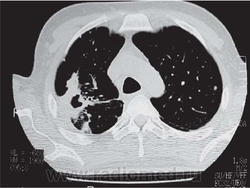

Родококкоз, как правило, встречается у лошадей и жеребят. Человек родококкозом не болеет. Но, у пациентов со СПИДом родококкоз встречается, и описано значительное количество случаев с легочными изменениями, вплоть до "кавитаций".